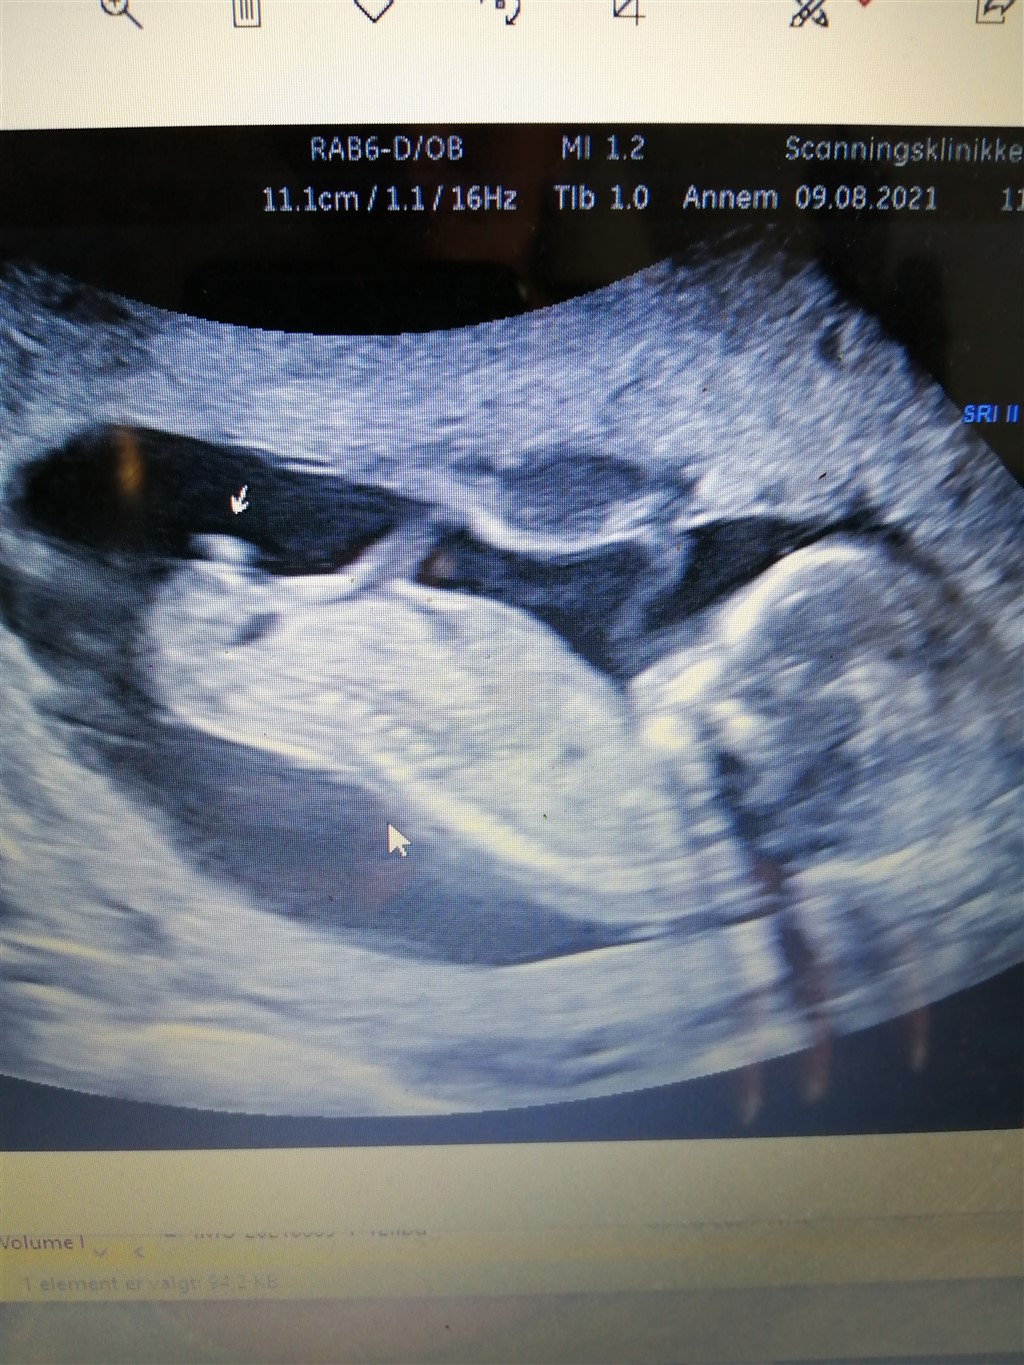

Hej! Jeg ved godt at det er en år gammel tråd, men var det så en pige der kom ud ♀️ jeg synes godt nok at dit billede ligner mit, som jeg fik taget til kønsscanning 14+6, hvor hun sagde at det klart og tydeligt var en dreng! Ligner det ikke altså på billedet i sædestilling. Synes dog sagtens jeg kan se tissemanden på det andet billede